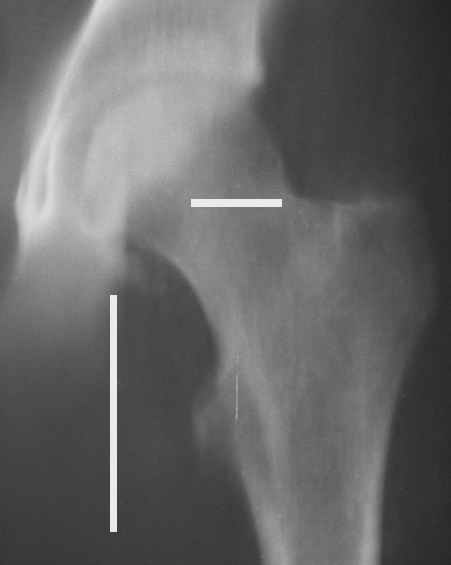

Уважаемые коллеги! Заканчивая обследование больного с переломо-вывихом бедра сделал ему обычные R-томограммы. Кажется удалось "поймать" и отломок и донорское место. Мои выводы - в скиаграмме. Считаю, что это передне-нижний фрагмент головки, образовавшийся вследствии отрывного перелома. На томограммах отломок обозначаю длинной стрелкой, а место откуда он оторвался - более короткой. Учитывая тот факт, что его размеры по КТ 25 х 15 мм считаю, что его фиксация на место необходима для профилактики артроза, что при 16-ти летнем возрасте пациента важно в плане максимального отодвигания эндопротезирования. Планирую оперировать его 24.05.05 г. Результаты представлю.

Несколько соображений к "картинкам". На прямом снимке и КТ-томограммах все типичные линии вертлужной впадины: крыша, передняя стенка, задняя стенка - сохранены. На КТ-сканах 6 и 7 появляется фрагментация головки. С учетом R-томограмм отломок расположен спереди-снизу, а не сзади-сверху от сустава, как написано в описании КТ.